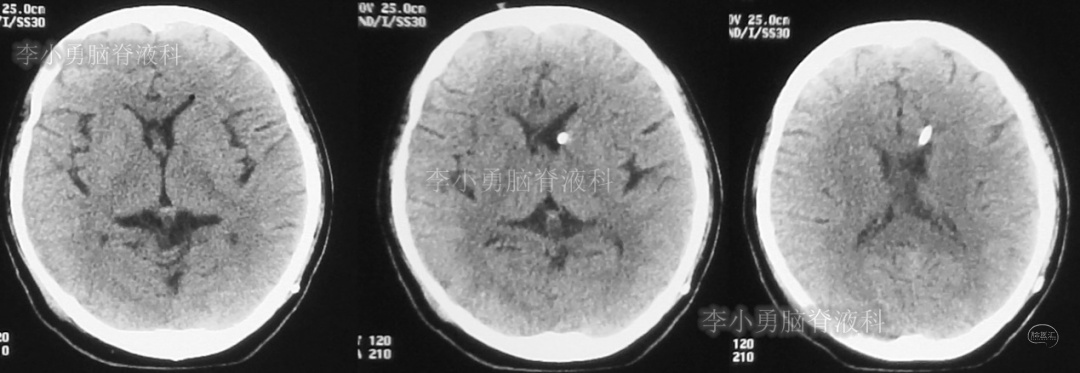

此后1个多月(2019年11月4日到2019年12月16日),患者意识一直无改善,一直呈模糊状态,多次复查头颅CT(图-12至图-20)见脑室大小反复变化不定,医生根据CT结果等反复多次调节分流泵压力(具体过程家属回忆不起)。但患者病情无好转却逐渐加重,逐渐不能咀嚼、吞咽及进食,卧床不起。

图-12:2019年11月8日头颅CT

图-13:2019年11月16日头颅CT

图-14:2019年11月19日头颅CT

图-15:2019年12月3日头颅CT

图-16:2019年12月10日头颅CT

图-17:2019年12月12日头颅CT

图-18:2019年12月13日头颅CT

图-19:2019年12月14日头颅CT

图-20:2019年12月16日头颅CT